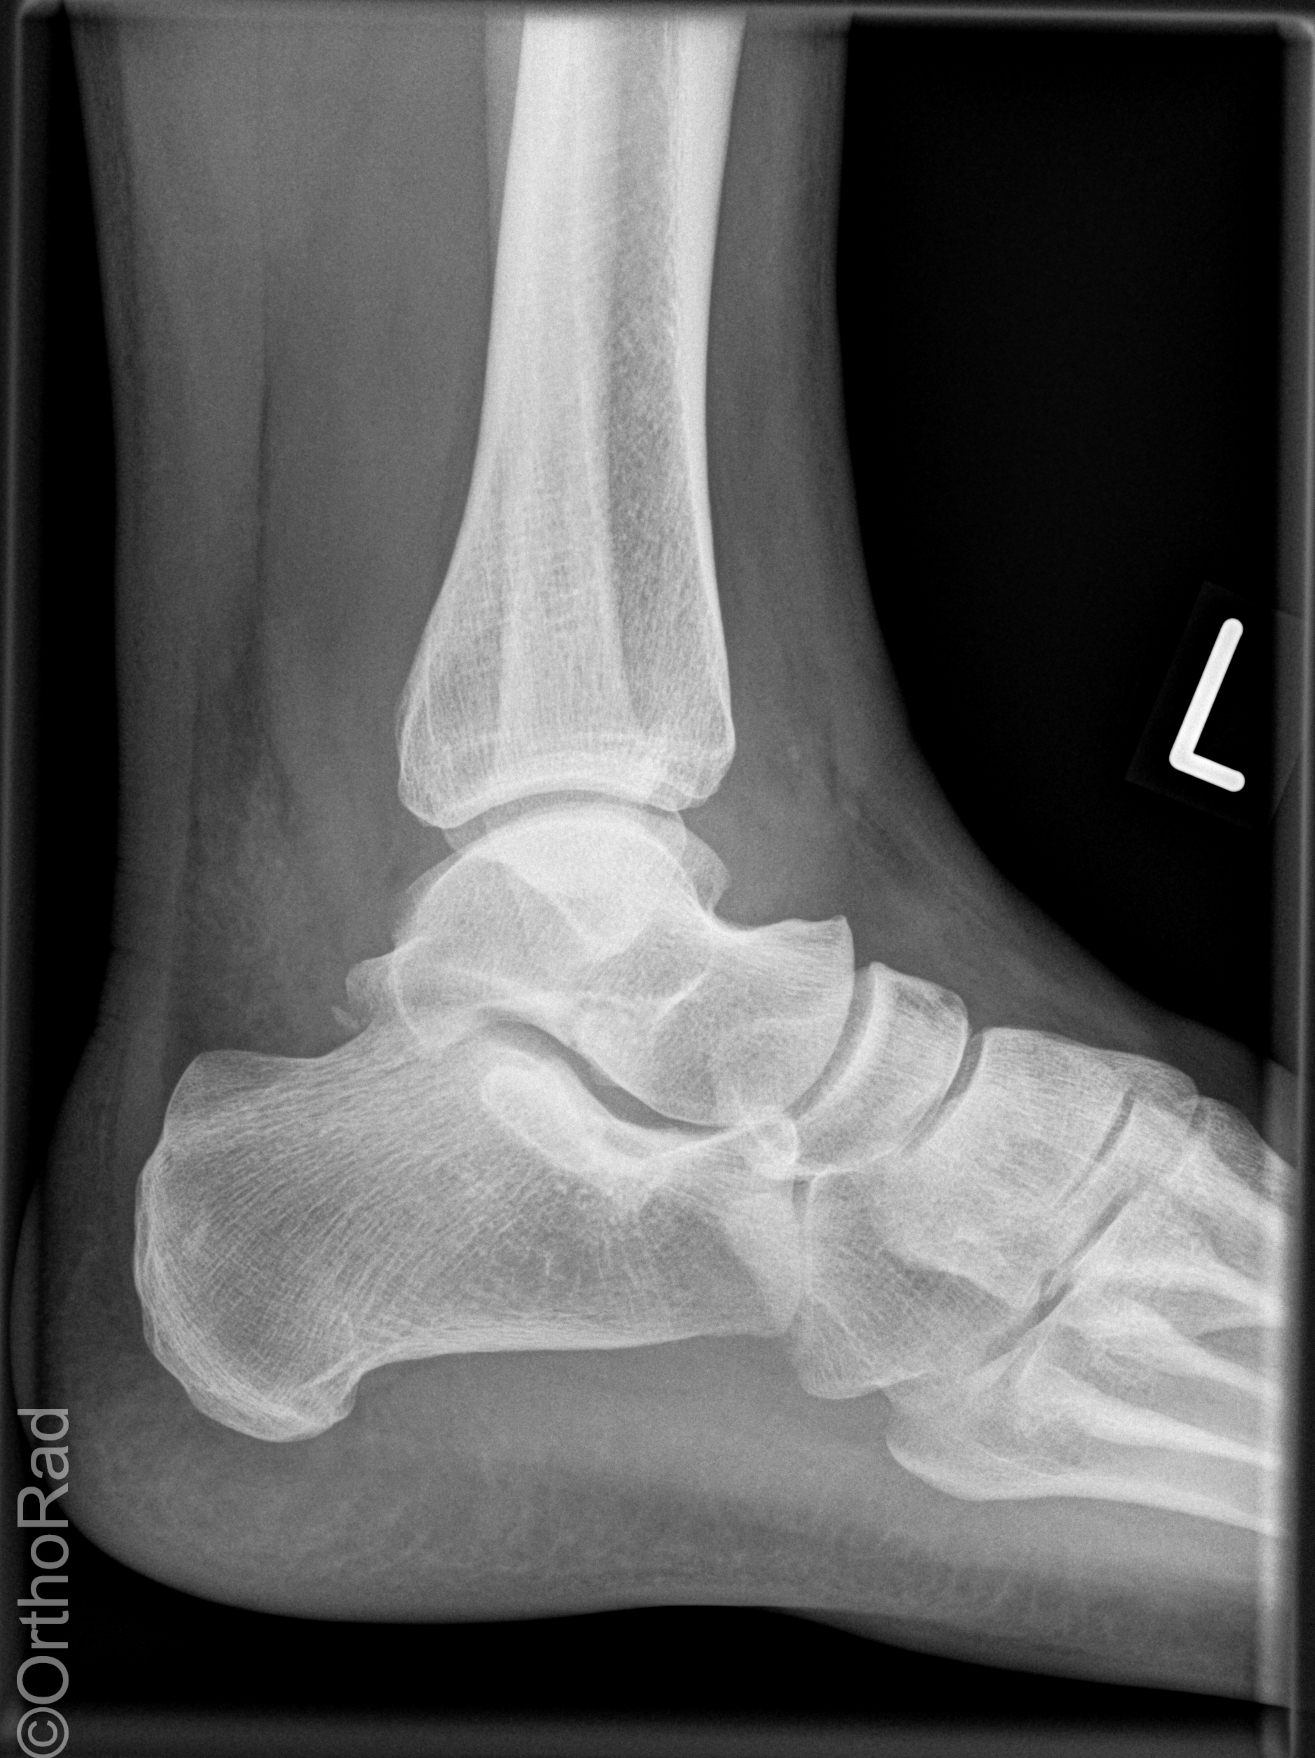

Snowboard fracture Talus